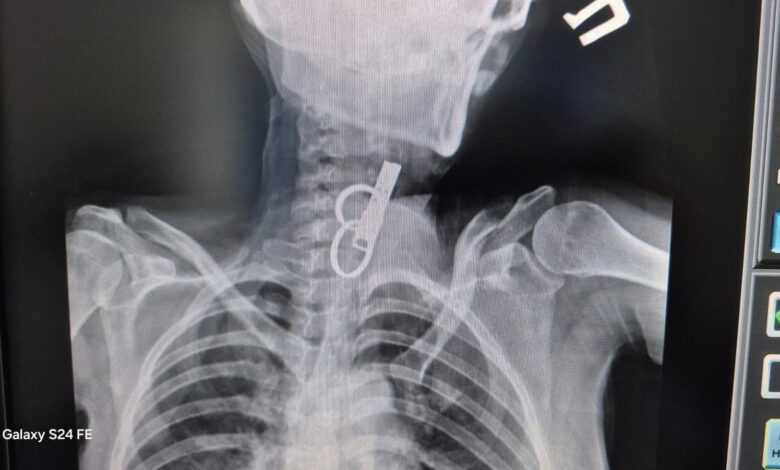

Ювелірна робота хірургів: на Гусятинщині врятували пацієнта, який проковтнув зв’язку ключів

В одній із комунальних лікарень на Тернопільщині рятували життя пацієнту, який проковтнув ключі.

“Завдяки наявності сучасного ендоскопічного обладнання та злагодженій роботі команди фахівців у закладі успішно проведено ендоскопічне видалення великого стороннього тіла зі стравоходу без виконання хірургічного розрізу. Стан пацієнта після втручання стабільний, самопочуття задовільне. Після перебування у відділенні анестезіології та інтенсивної терапії пацієнта переведено до загальнохірургічного відділення для подальшого лікування та медичного спостереження. Операційну команду склали – хірург — Садовий О.М., асистент — Малкович О.Й., лікар-анестезіолог — Чулик М.С”, –йдеться у дописі лікарні.